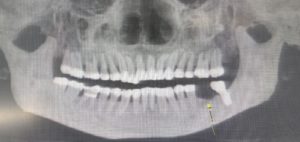

午後のオペ

右下5、6番の欠損に対してストローマンSPインプラントを植立しました。

大体毎回1本10分間ぐらいで終わります。 今回は2本で20分間です。